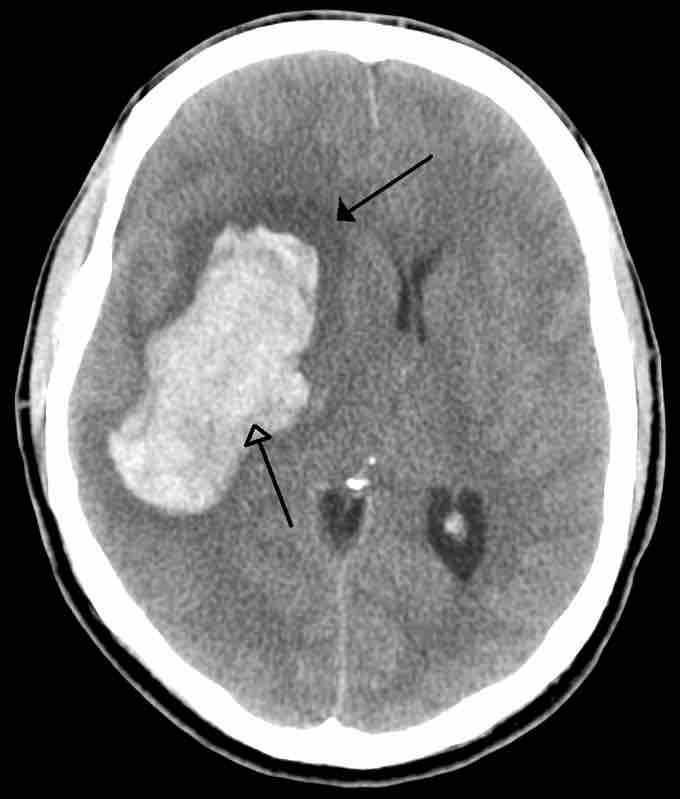

An Example of a Stroke

A intra-parenchymal bleed with surrounding edema.